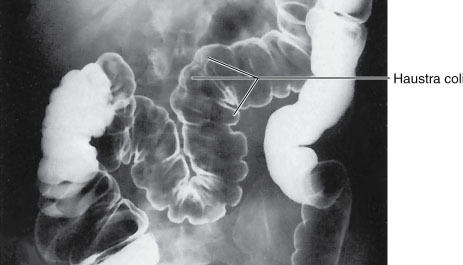

What are haustra and where are they found?

Haustra are small pouches/sacculations which gives colon segmented appearance. As a result of contraction of longitudinal muscle